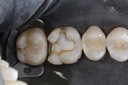

Scott Kanamori #14 finish

Scott Kanamori #14 buccal